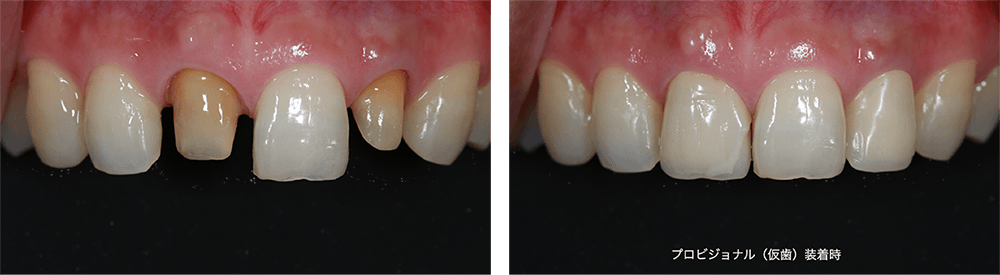

1. 右上と左上前歯を形成→仮歯装着→仮歯調整

2. オフィスホワイトニング2回

3. 変色したレジン部分をダイレクトボンディング法でやりかえ

4. 右上、左上のセラミックを装着

プロビジョナル(仮歯) 77,000円(税込)